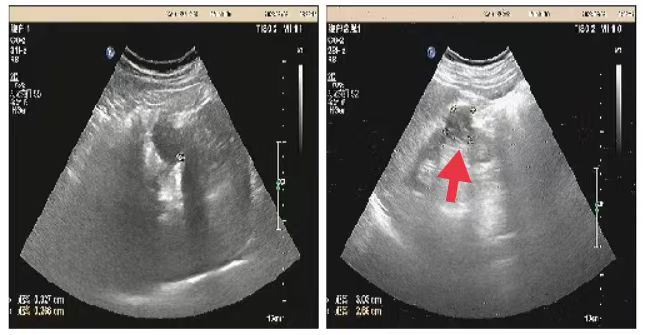

05、**女士,54岁

于2023年8月16日在邯郸仁泰东区体检,膀胱彩超检查提示:膀胱内可见高回声团1.8*1.4cm,边界欠清、形态不规则,内回声不均匀,随体位改变移动不明显。CDFI:周边可见少量血流信号。2023年8月17日首次回访,通知客户到三甲医院进一步检查。2023年8月30日跟踪回访,客户家属告知,在北大医院复查,结果与我院一致,已在北大医院完成手术治疗,现出院在家休养。

09、**男士,55岁

于2023年8月6日在邢台仁泰体检部体检,腹部彩超检查提示:右肾实质部可探及大小约3.0*2.7cm低回声包块,CDFI:周边可见少许血流信号。考虑:右肾内占位性病变。建议客户到三甲医院进一步检查,明确病变性质。2023年8月12日跟踪回访,客户已在河北医科大学第二医院手术治疗。